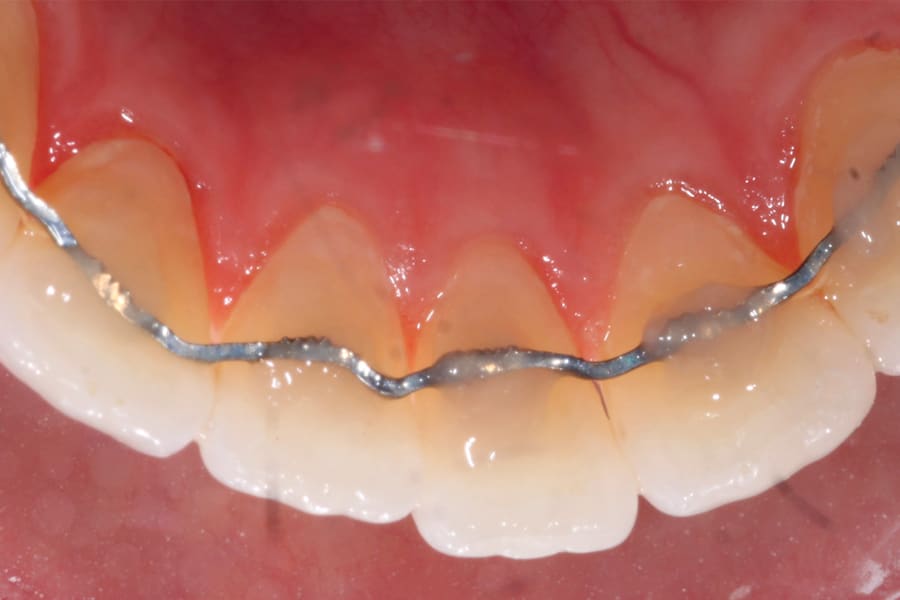

A popular example of this approach is the twisted stainless-steel wire retainer (Figure 1). This design features ease of fabrication and placement as well as minimal cost. Frequently, a twisted lingual retainer can be fabricated chairside and placed immediately with no preparation, impressioning, or laboratory fabrication required. Consequently, this design is commonly utilized. It can be made from a very thin wire (such as a .009" ligature tie) that is folded over and spun down (or twisted) then formed to the arch curvature and direct bonded. Annealing the formed wire prior to placement can be beneficial, as this can remove the "memory" that stainless steel possesses if not permanently deformed.

There are, however, some unfavorable long-term ramifications of this design. Due to the nature of stainless steel, which has memory and over time will partially return to its original shape, these twisted lingual retainers may "unwind" or uncoil and exert unintended forces on the teeth to which they are bonded (Figure 5 and Figure 6, Figure 8 through Figure 11, Figure 14 through Figure 16). This leads to excessive labial or lingual root torquing movements, often resulting in highly undesirable recessions, dehiscences, and fenestrations. Because it may take years for this occurrence to manifest, the orthodontist (who usually places the retainer) is typically both unaware of the situation, as he or she does not customarily follow patients for such long-term periods, and free of blame. The periodontal implications of this outcome can be highly detrimental, as seen in the cases presented herein.

Obviously, more suitable and reliable fixed lingual retention designs are needed, and, fortunately, many are available. As described above, the twisted chairside fabricated design can be unreliable. A well-suited alternative is a passive braided design as shown in Figure 2 (Ortho FlexTech® stainless steel, Reliance Orthodontics, relianceorthodontics.com). The braided design does not uncoil over time. The lingual retainer is placed in passive fashion after being cut to the proper length from a spool and bonded to the appropriate teeth. This relatively inexpensive alternative is fabricated chairside with no laboratory intervention or special preparation required. One potential downside is that it is a relatively bulky option.